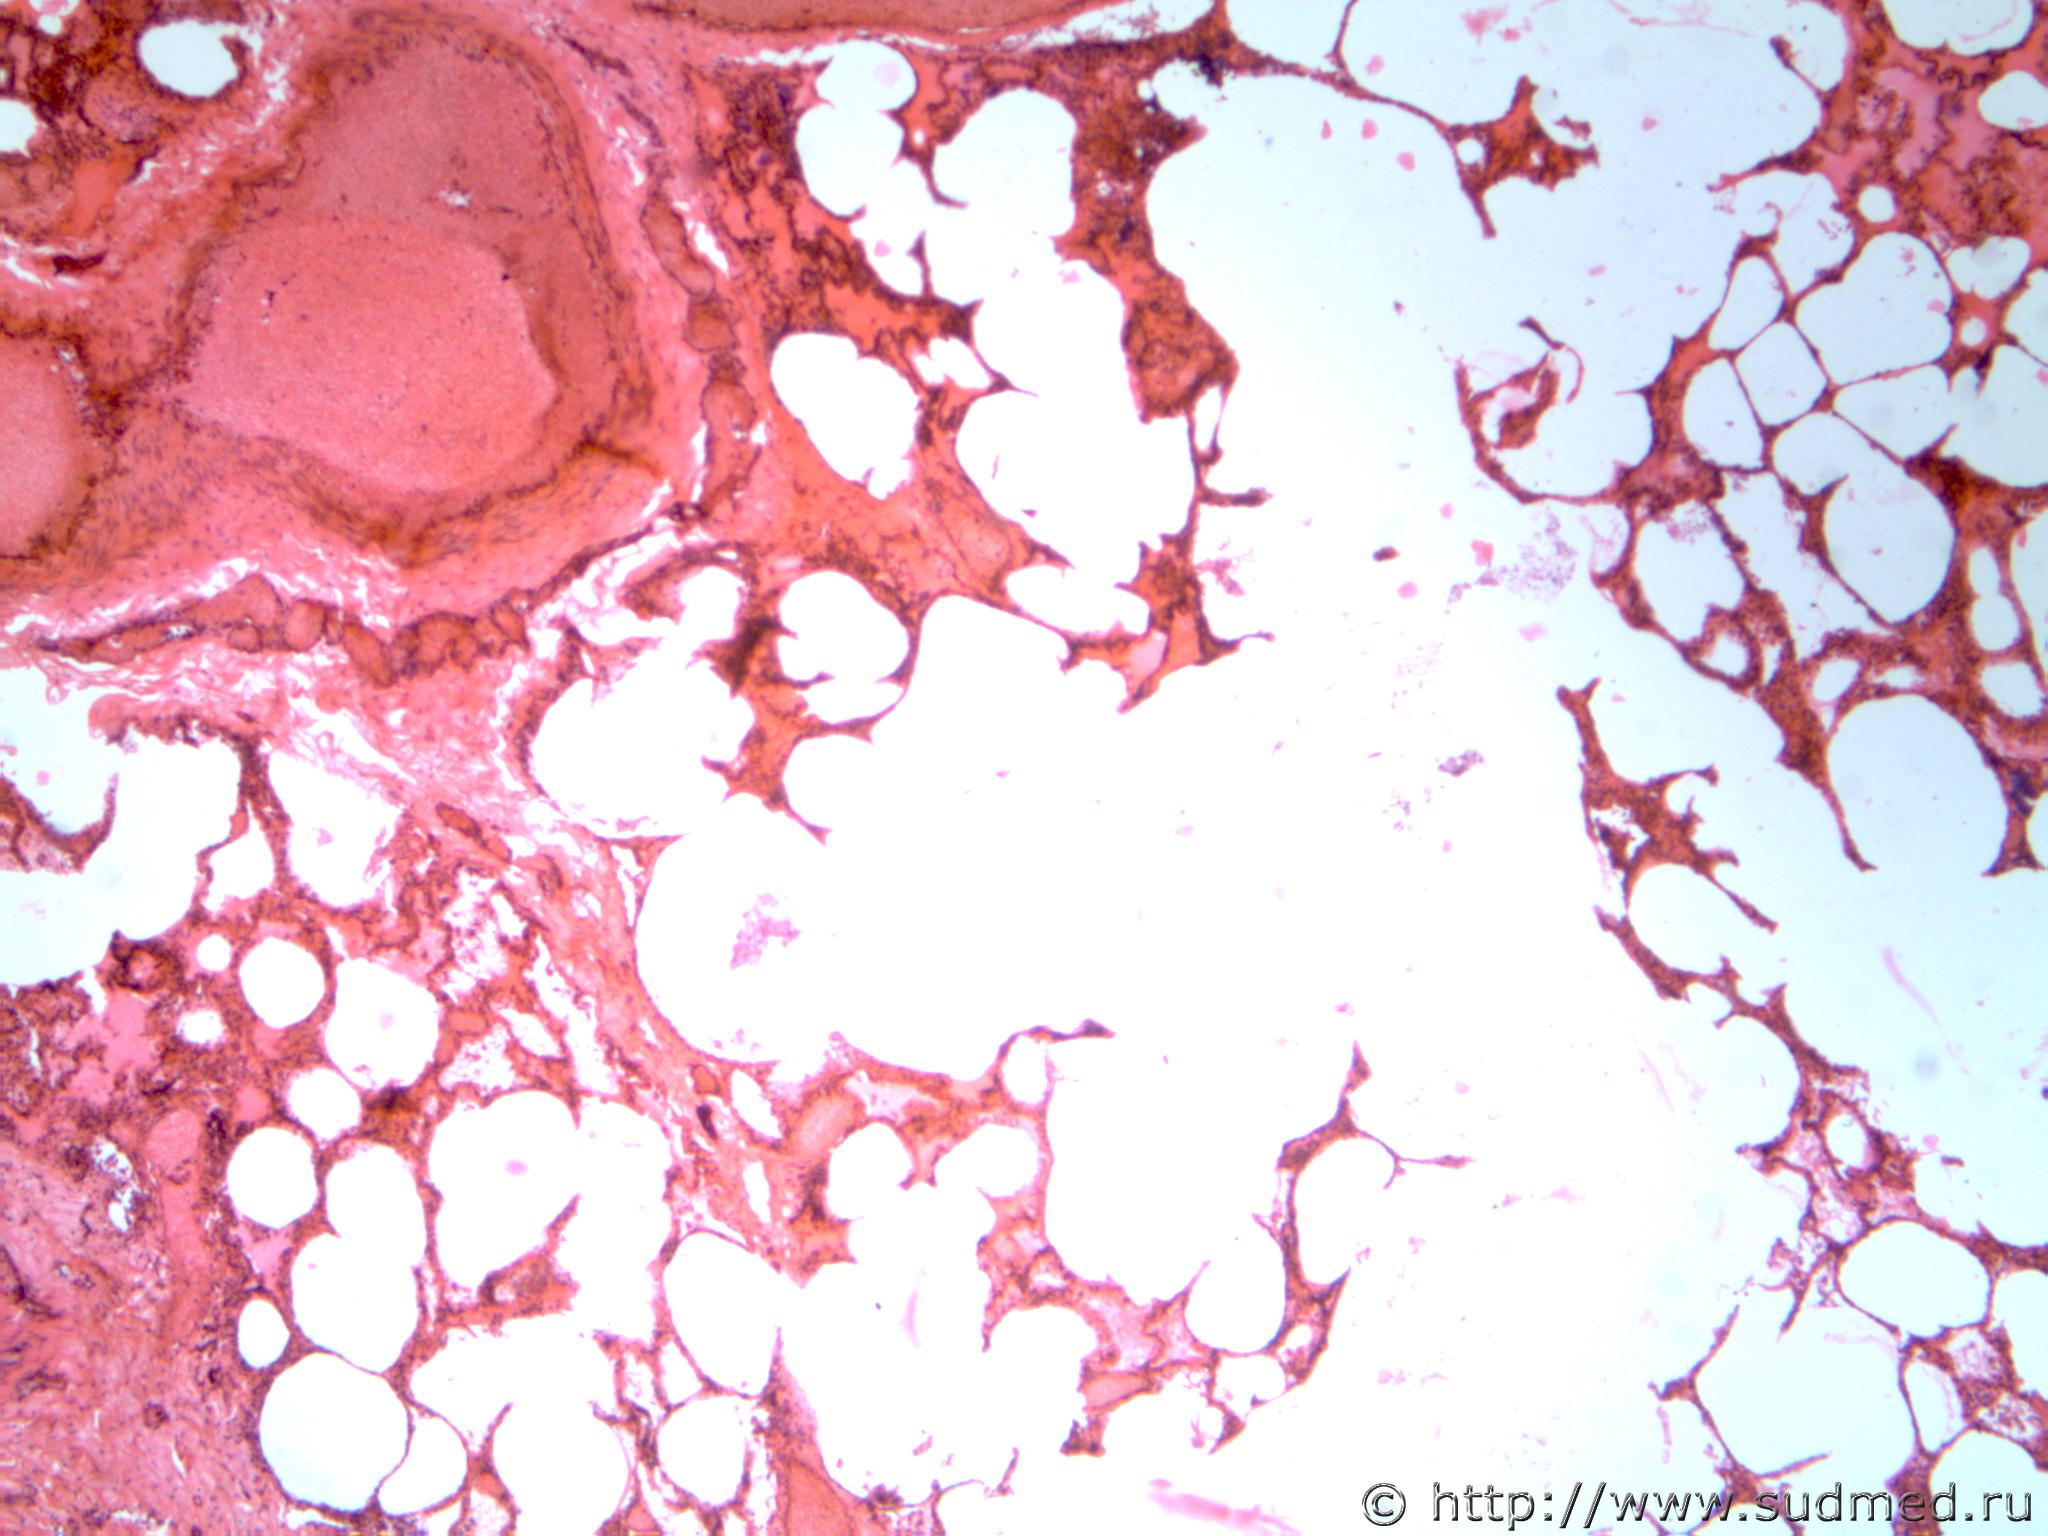

Аспирация желудочным содержимым (рвотными массами) и острая эмфизема, венозное полнокровие легких